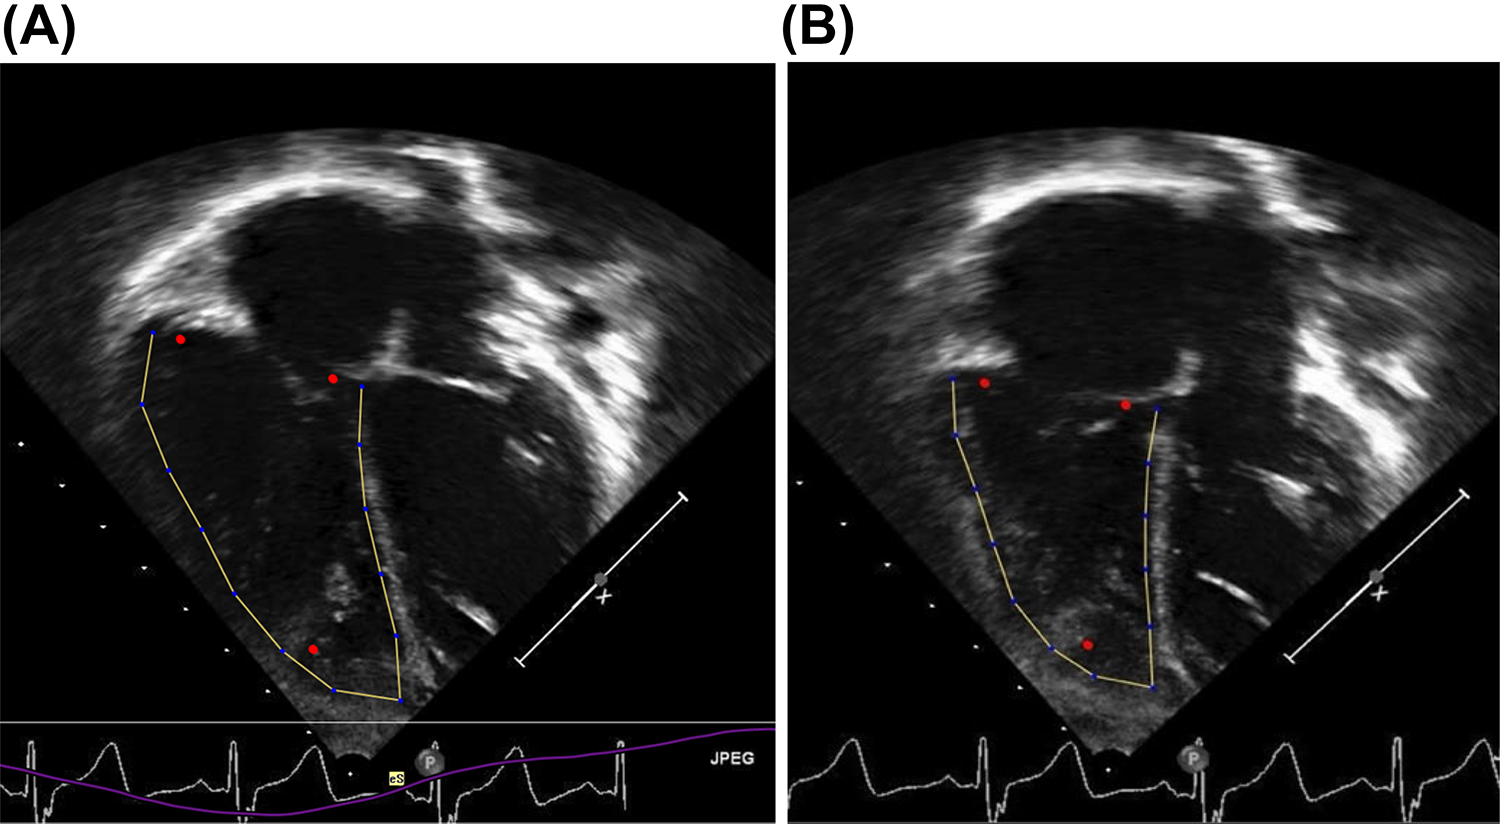

Double chambered left ventricle: an incidental rare congenital heart disease. Report of a case within the context of a literature review

Double-chambered left ventricle (DCLV) is an extremely rare congenital heart disease in which a muscular band or fibromusc...

International Journal Of Cardiovascular Imaging